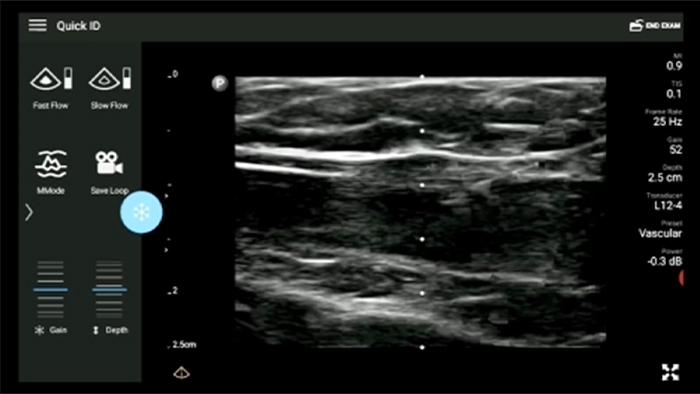

Onderzoeksresultaten binnen handbereik

Met Lumify kunt u de onderzoeksresultaten en -beelden van patiënten eenvoudig direct vanaf uw compatibele Android- of iOS-apparaat opslaan en openen. U kunt de resultaten zelfs delen met collega's voor een betere samenwerking.

Lumify kan helpen de subtiele details van een beeld zichtbaar te maken en afwijkende weefselstructuren bloot te leggen vanuit verschillende hoeken. Hierdoor kunt u met vertrouwen realtime beslissingen nemen, van diagnose tot herstel.